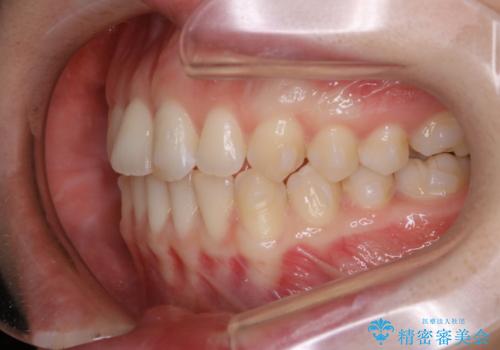

- 上下前歯のがたつきが気になるとご相談にいらした方です。

一見前歯のがたつきだけ改善させれば良い様に見えますが、このがたつきの原因は奥歯の嚙み合わせのズレからくるものであったため、インビザラインFULLで噛み合わせの改善から行っていきました。前歯の角度も改善されたために頑張って唇を閉じる必要がなくなり、横顔のシルエットも綺麗になりました。

前歯のがたつきだけを治そうとした場合、噛み合わせは二の次なってしまう事が多く、せっかく綺麗になった歯並びも後戻りしやすくなります。奥歯の噛み合わせからしっかり機能させることで、長期間にわたって綺麗な歯並びを保ちやすくなります。